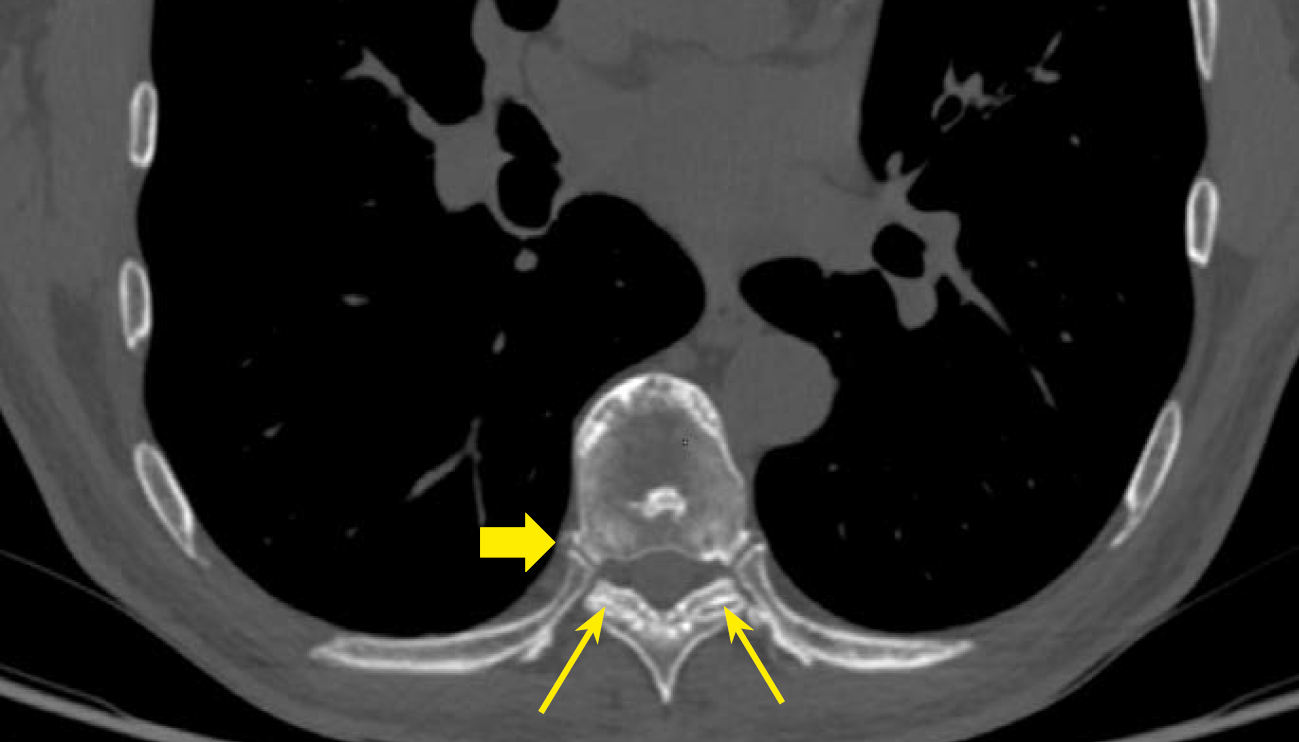

В нашем исследовании проведен анализ патологии позвоночника и суставов у пациентов с акромегалией. Спондилоартроз выявлен почти у всех пациентов — 95,9%, чуть реже визуализирован ОА реберно-позвоночных суставов 89,8% и ОА грудино-реберных суставов в 75,9% случаев (табл. 3, рис. 2–5).

Рисунок 2. МСКТ пациента А. с акромегалией 37 лет, аксиальная проекция (склероз субхондральных отделов с сужением суставной щели, тонкие стрелки), ОА реберно-позвоночных суставов (склероз субхондральных отделов с наличием остеофитов, толстая стрелка).

Figure 2. MSCT of patient A. with acromegaly, 37 years old, axial view (sclerosis of subchondral regions with joint space narrowing, thin arrows), OA of costovertebral joints (sclerosis of subchondral regions with osteophytes, thick arrow).